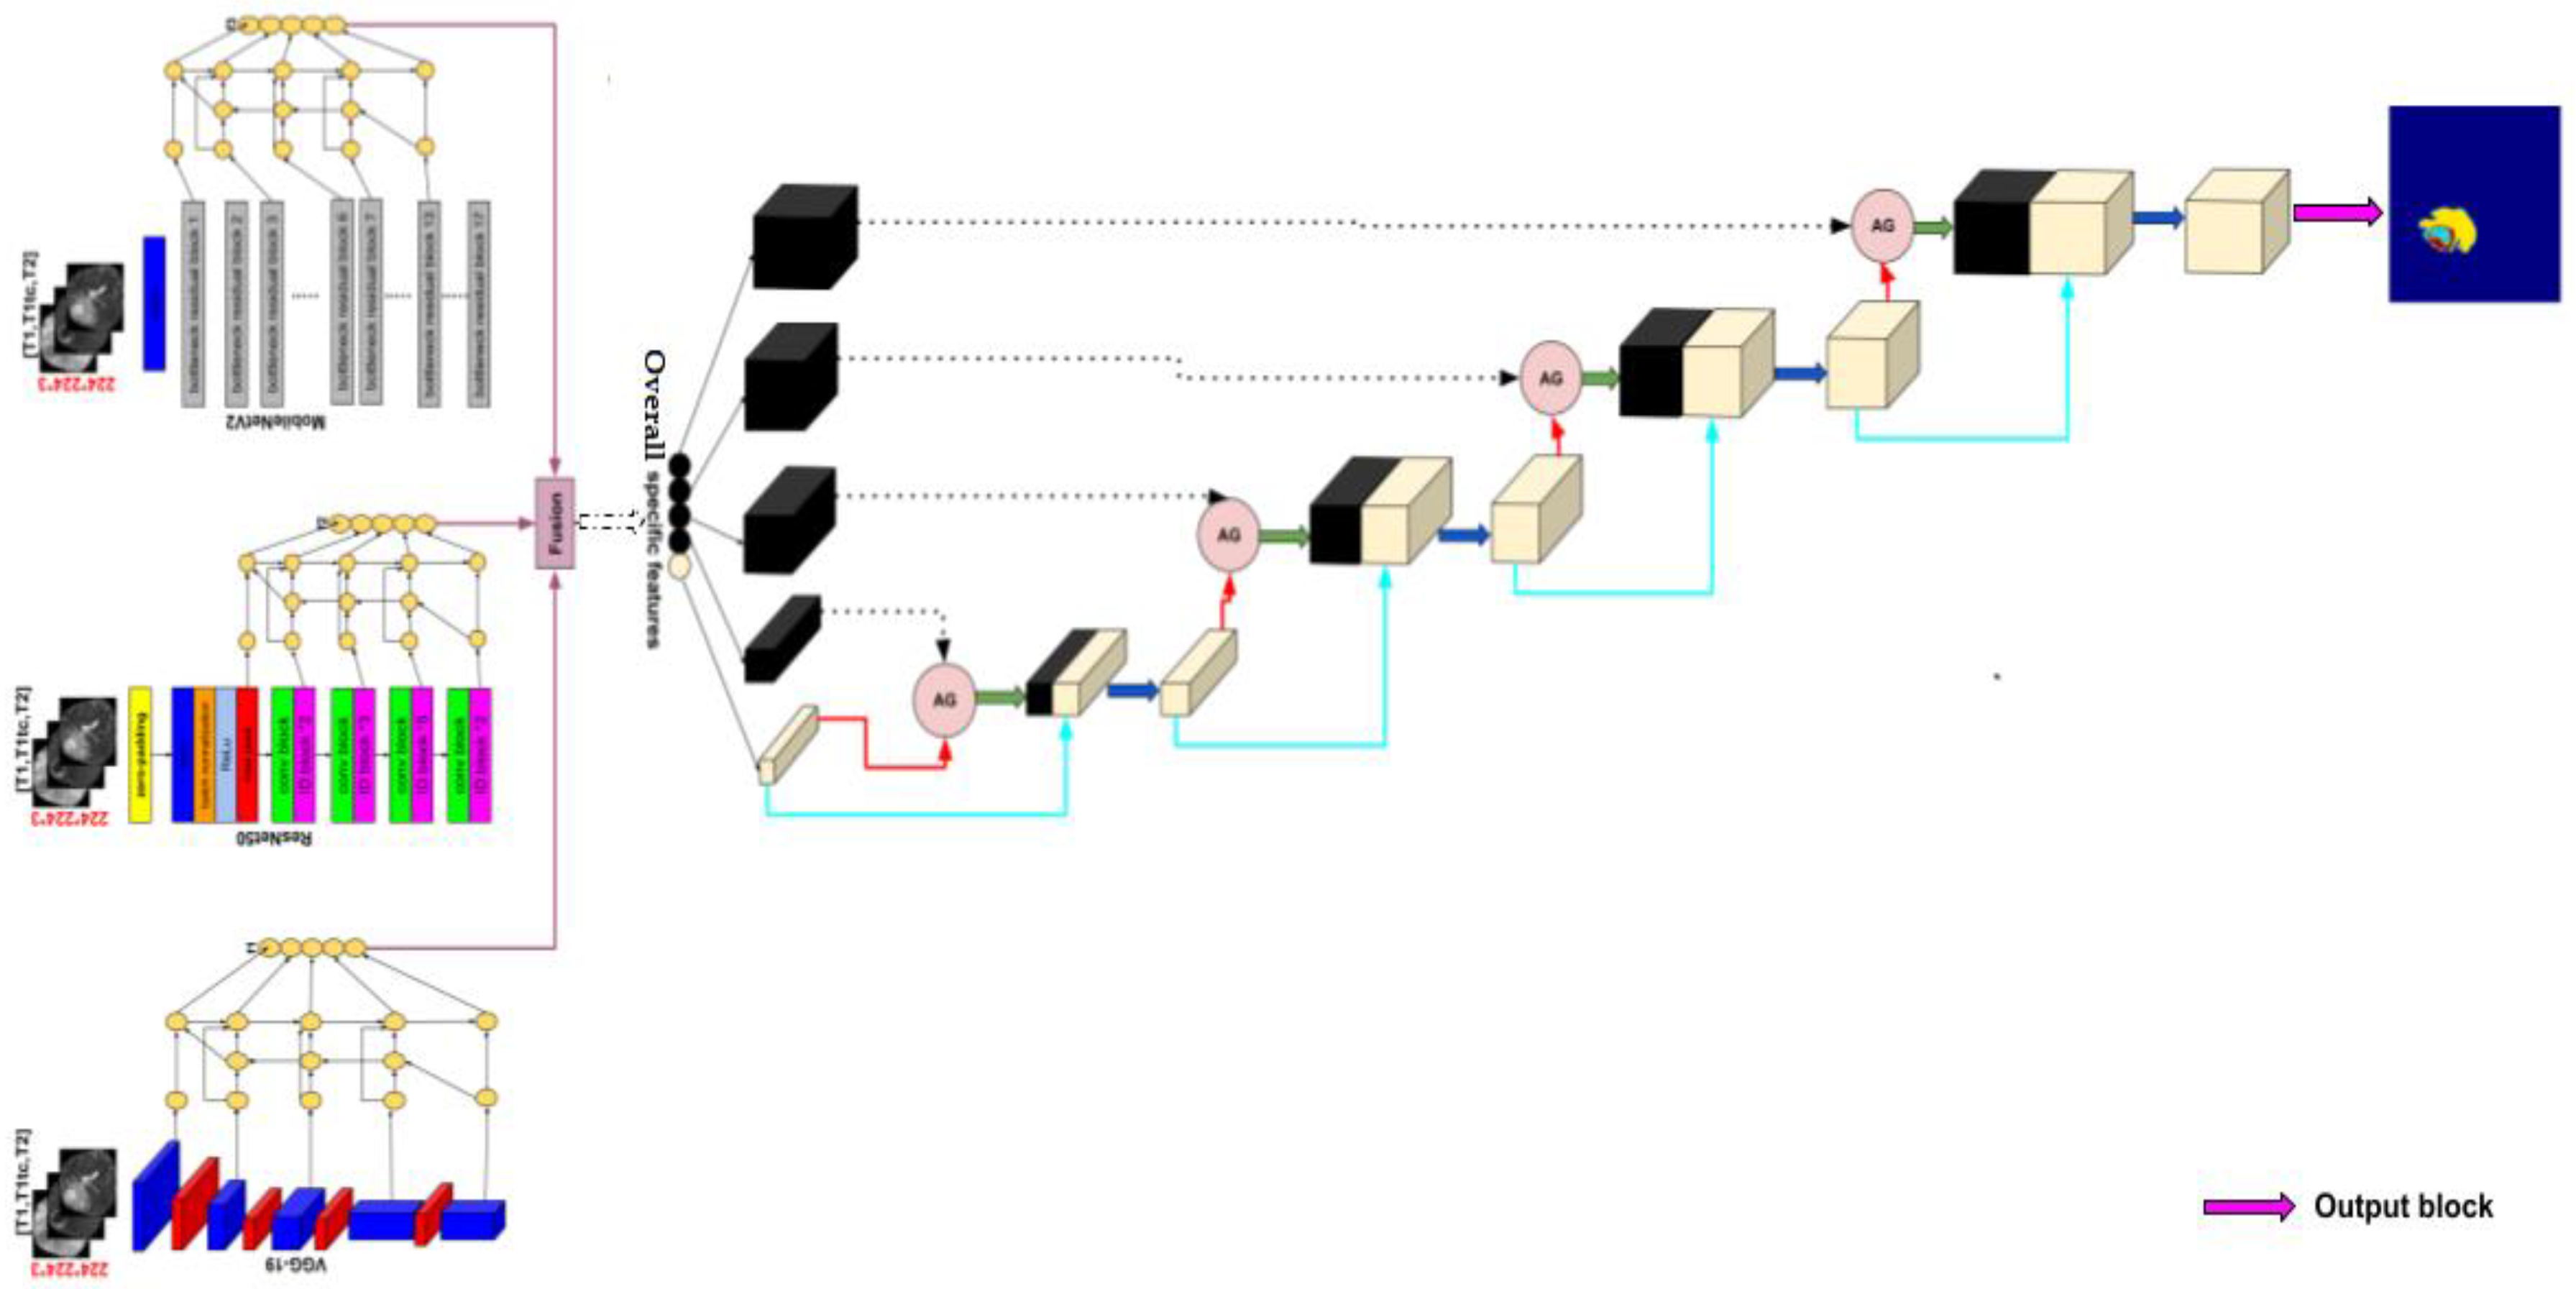

2.2. Methods

2.2.1. Encoder

Transfer Learning

- VGG-19

- ResNet50

- MobileNetV2

Bi-Directional Feature Pyramid Network (Bi-FPN)

2.2.2. Decoder

| Layer | Output Size |

|---|---|

| Input | (224,224,3) |

| VGG-19 + BiFPN 1 | [(224,224,32), (112,112,32), (56,56,32), (28,28,32), (14,14,32)] |

| MobileNetV2 + BiFPN 2 | [(224,224,32), (112,112,32), (56,56,32), (28,28,32), (14,14,32)] |

| ResNet50 + BiFPN 3 | [(224,224,32), (112,112,32), (56,56,32), (28,28,32), (14,14,32)] |

| Fusion of 1, 2, and 3 | [(224,224,32), (112,112,32), (56,56,32), (28,28,32), (14,14,32)] |

| Attention decoder | (224,224,128) |

| Output | (224,224,4) |